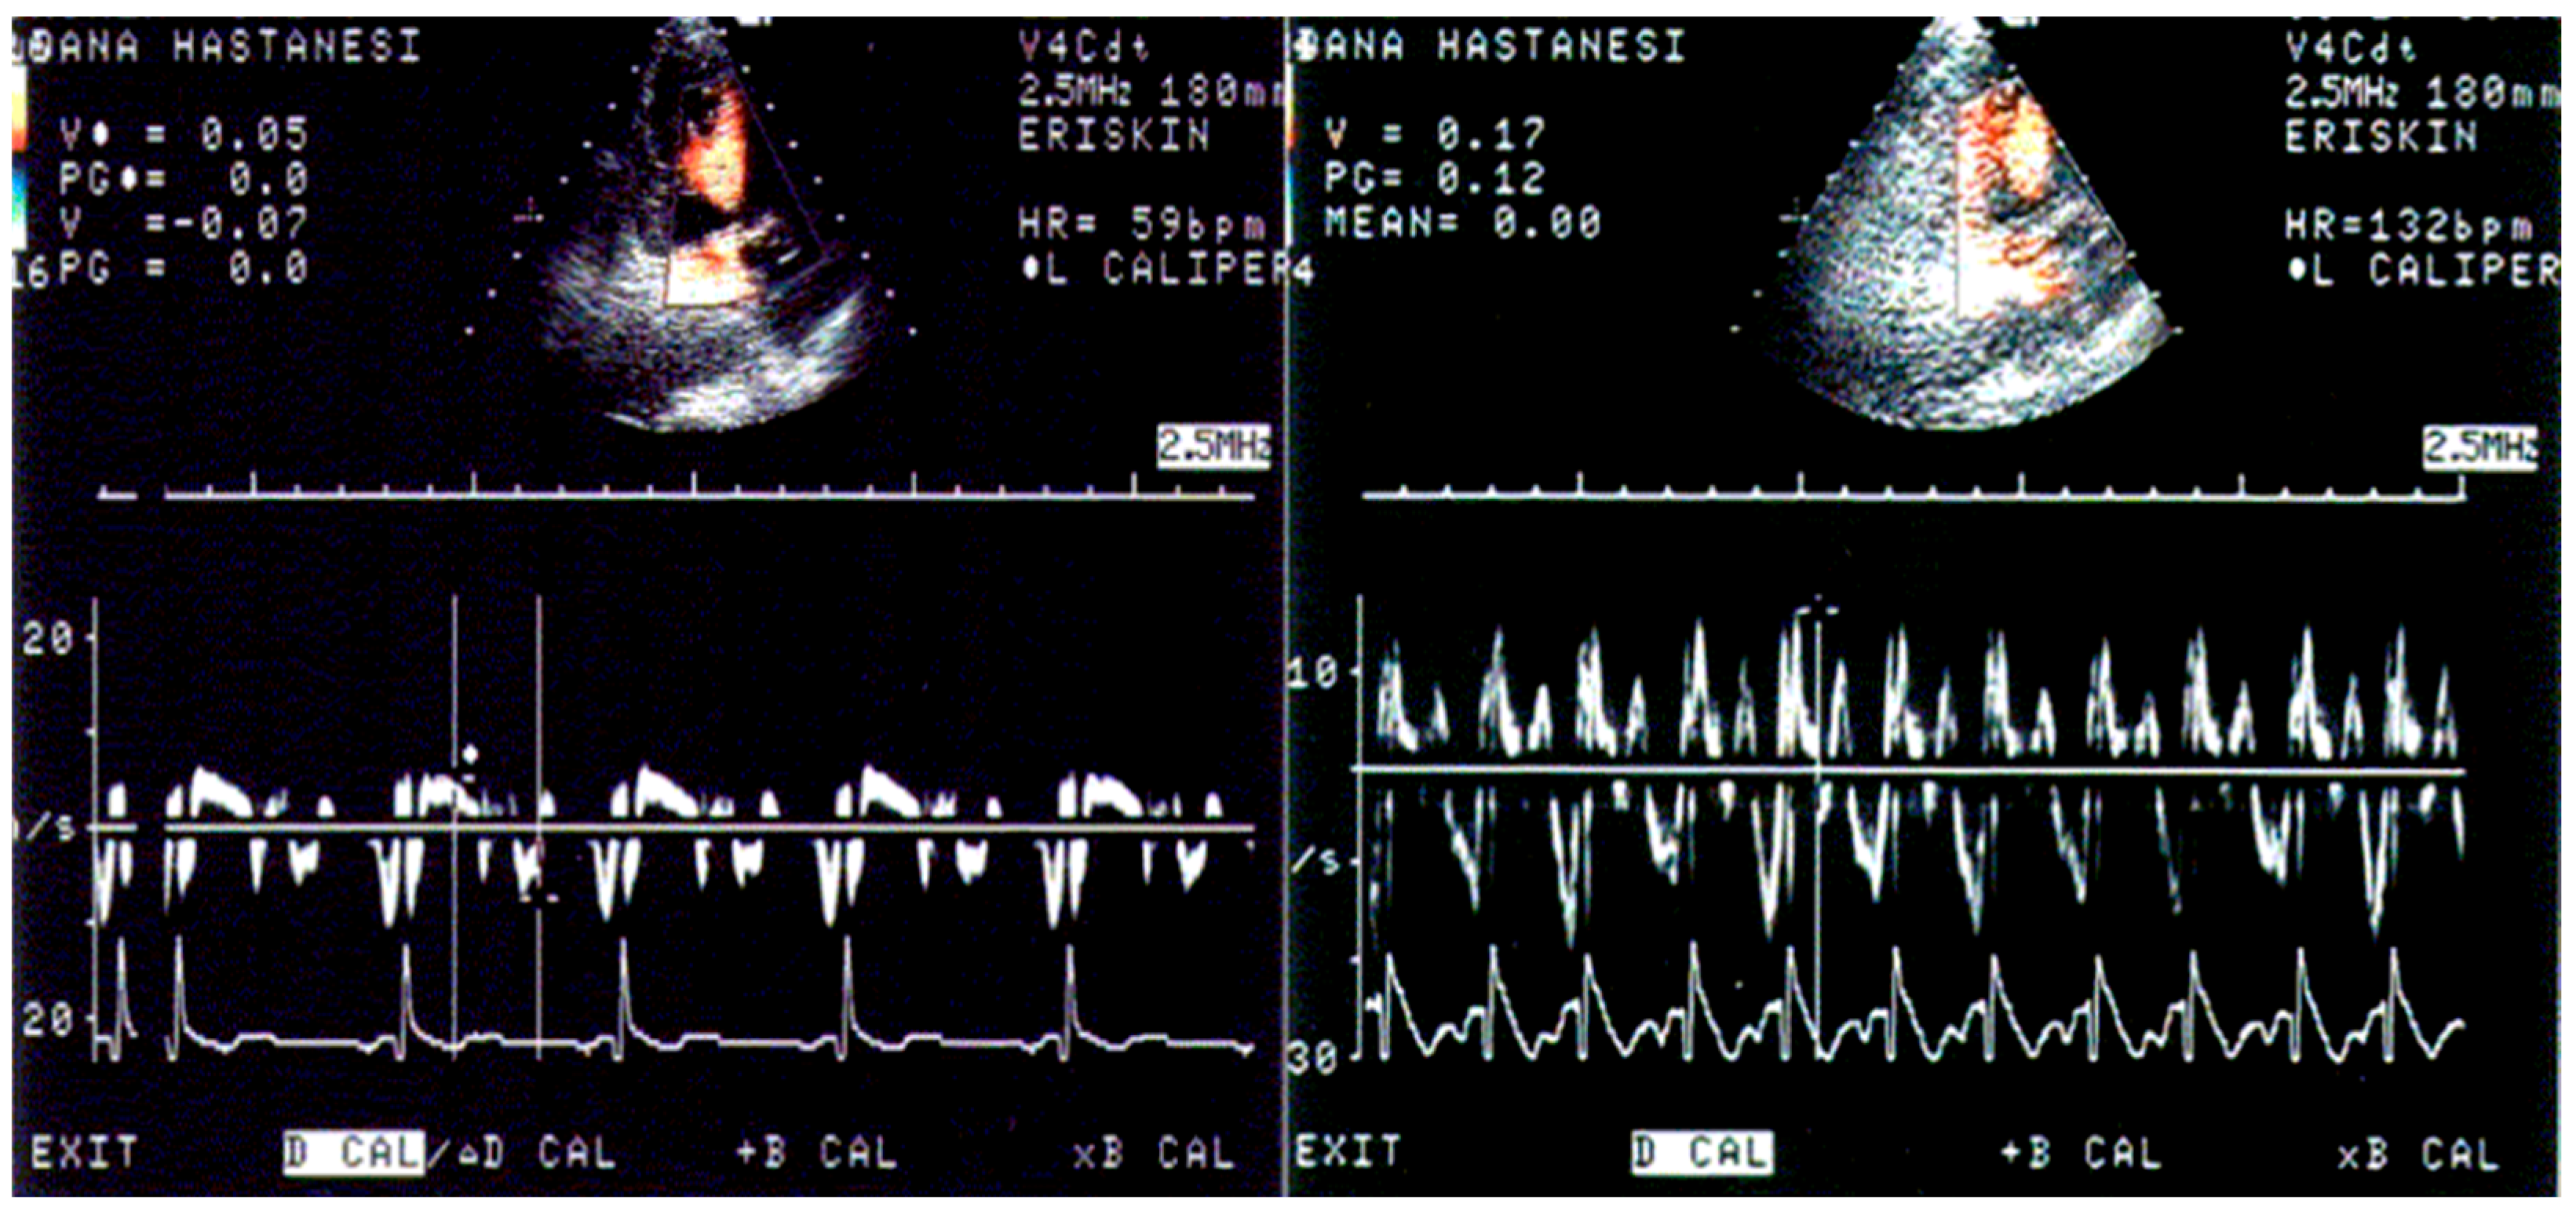

- Yalçin, F.; Yiǧit, F.; Erol, T.; Baltali, M.; Korkmaz, M.E.; Müderrisoǧu, H. Effect of Dobutamine Stress on Basal Septal Tissue Dynamics in Hypertensive Patients with Basal Septal Hypertrophy. J. Hum. Hypertens. 2006, 20, 628–630. [Google Scholar] [CrossRef]

- Yalçin, F.; Yalçin, H.; Küçükler, N.; Abraham, T.P. Quantitative Left Ventricular Contractility Analysis under Stress: A New Practical Approach in Follow-up of Hypertensive Patients. J. Hum. Hypertens. 2011, 25, 578–584. [Google Scholar] [CrossRef][Green Version]

- Yalçin, F.; Muderrisoglu, H.; Korkmaz, M.E.; Ozin, B.; Baltali, M.; Yigit, F. The Effect of Dobutamine Stress on Left Ventricular Outflow Tract Gradients in Hypertensive Patients with Basal Septal Hypertrophy. Angiology 2004, 55, 295–301. [Google Scholar] [CrossRef] [PubMed]